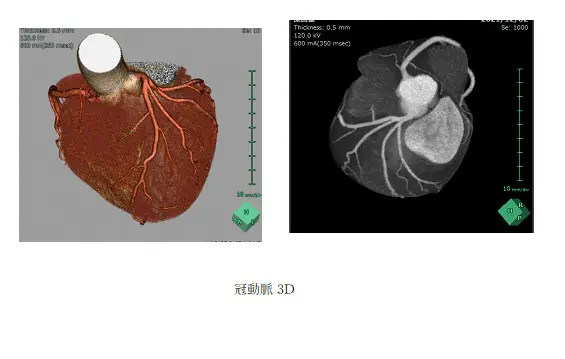

検出器の多列化により短時間に広範囲の撮影が可能となりました。また1度の撮影で様々な断面画像を得られます。得られた画像をワークステーションで解析することで3D画像を作成できます。

造影剤を使用することで病変や血管を詳細に描出できるため病変部の血管走行を把握することができます。血管走行の3Dは手術プランに役立てられます。- 腰部血管3D

- 頭部動静脈3D

2021年11月よりキヤノンメディカルシステムズ社製Aquilion ONE NATURE を稼働しています。0.5mm×320列の検出器を搭載しており、X線1回転で16cmの幅を最短0.275秒で撮影できます。脳や心臓などは1回転で臓器全体を撮影できます。

また、深層学習(AI)による画像再構成や逐次近似再構成により被ばく線量を低減して検査ができます。-

心臓(冠動脈)CT検査

- 心臓を栄養する冠動脈を検査することができます。これまでは狭心症や心筋梗塞といった冠動脈の狭窄や詰まってしまう病気の診断は、最終的には心臓カテーテル検査を行うしかありませんでした。心臓カテーテル検査は手や足の動脈からカテーテルを入れてそこから造影剤を注入しX線を照射しながら行う検査で入院の必要もあります。しかし、心臓CT検査は外来で検査することができ、患者さまの負担が少なくてすむことが特徴です。心臓CT検査で狭くなっている冠動脈を発見して心筋梗塞になる前に治療することができます。冠動脈CT検査の長所と短所

2021年11月より稼働している320列CTでは数秒の息止めで心臓全体を撮影できるため検査時間が短く、従来よりも患者さまの負担が少なくなっています。